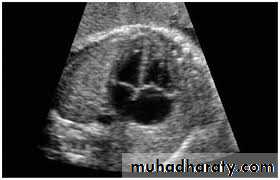

Antenatal diagnosis

Fetal anomaly scan is performed between 18 and 20 weeks' gestation. If an abnormality is detected, detailed fetal echocardiography is performed by a paediatric cardiologist, who also checks any fetus at increased risk, e.g. where Down's syndrome is suspected, where the parents have had a previous child with heart disease or where the mother has C.H.D. The continuation of pregnancy and delivery then planned.